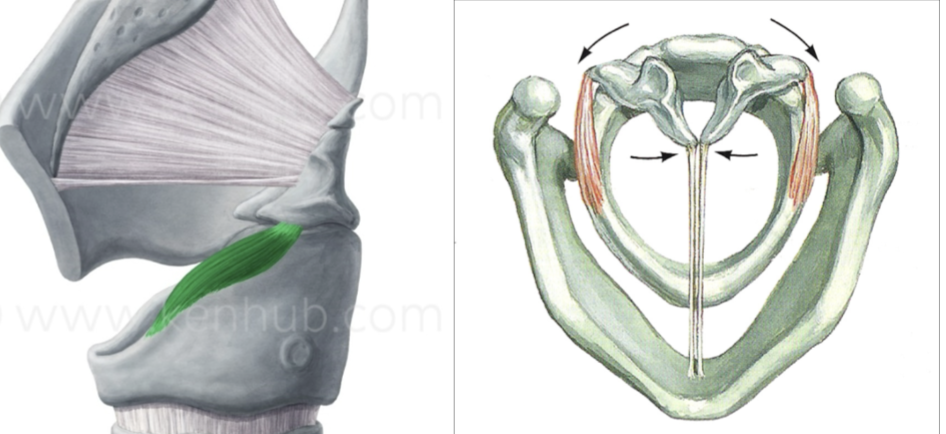

What is this muscle?

Lateral cricoarytenoid (LCA) (adduct VF)